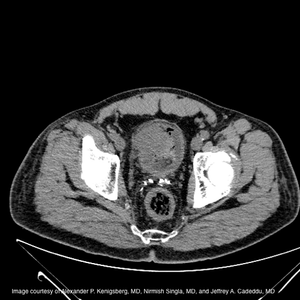

A 63-year-old African-American male presents to the emergency department with sudden onset of painless gross hematuria for one day. He reports dark red urine with clots causing occasional dysuria, difficulty emptying, and light-headedness.

Published: September 3rd 2019 | Updated: